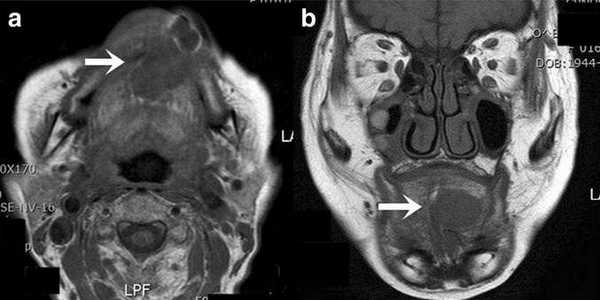

Не возникало сложностей в выявлении опухолевых узлов Т3, Т4 стадий, имевших все отмеченные выше признаки в различных сочетаниях в 36 исследованиях (рис. 11). Из 50 обследованных с помощью МСКТ и МРТ пациентов у 26 (52,0%) были выявлены метастазы в лимфатических узлах шеи. Поражались преимущественно лимфатические узлы I-II уровня. Признаками метастаза плоскоклеточного рака в лимфатических узлах были: увеличение размера лимфатического узла более 1,0 см, изменение формы лимфатического узла с бобовидной на округлую, структурные нарушения в узле, нечеткость наружных контуров узла, уплотнение окружающей жировой ткани на КТ или изменение сигнала на МРТ.

Рис. 10. А. Пациент Е., 52 года. МРТ полости рта, ротоглотки в аксиальной проекции, Т1-ВИ. Опухоль языка небольших размеров, границы визуализируются с трудом за счет перифокального отека (стрелки); В. Тот же пациент. МРТ в аксиальной проекции, Т2 с подавлением сигнала от жировой ткани. Визуализируются границы опухолевого узла, размеры опухоли языка четко определяются (стрелки)

Рис. 11: А. МРТ полости рта, ротоглотки в аксиальной проекции. Рецидив опухоли языка размерами 6,0х6,5 см с распространением на дно полости рта, правую боковую стенку ротоглотки (стрелки). Выявляется переход за среднюю линию; В. Тот же больной. МРТ полости рта, ротоглотки в коронарной проекции. Опухолевый узел показан стрелками. Просвет ротоглотки сужен, деформирован. Опухоль имеет низкий сигнал на Т1-ВИ, аналогичный сигналу от окружающих мышц, при этом размеры опухолевого узла, его объемные характеристики позволяют четко отграничить от интактных тканей. Также отмечается структурная неоднородность патологического образования за счет некроза

Большинство пораженных метастазами лимфатических узлов имели размеры более 1,0 см, округлую форму (рис. 12). Внутривенное контрастирование при оценке изменений в лимфатическом узле являлось обязательным условием для уточнения внутренней структуры и выявления зон некроза. В результате гипоксии и распада ткани формируется центральная зона некроза, не накапливающая контрастный препарат при внутривенном болюсном усилении. При этом отмечается повышение плотности в периферических отделах лимфатического узла (рис. 13).

Рис. 12. Пациент П., 68 лет. МРТ полости рта, ротоглотки в коронарной проекции. Выявляется увеличенный подчелюстной лимфатический узел округлой формы, неоднородной структуры (стрелки)